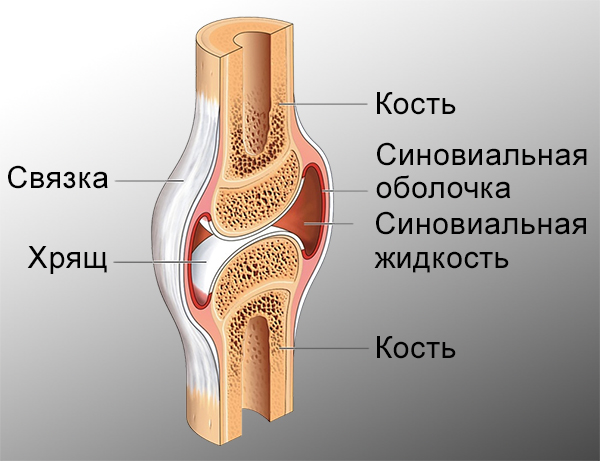

Рисунки Суставов: Анатомические Иллюстрации